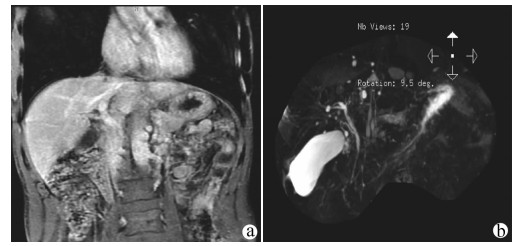

A case of splenic arteriovenous fistula with abdominal pain and gastrointestinal bleeding as the first symptoms

Yuanyuan CAI, Zhongwen WU, Juan LU

2021, 37(5): 1186-1188. DOI: 10.3969/j.issn.1001-5256.2021.05.043

Abstract(1011) HTML (291) PDF (2876KB)(49)

Abstract: